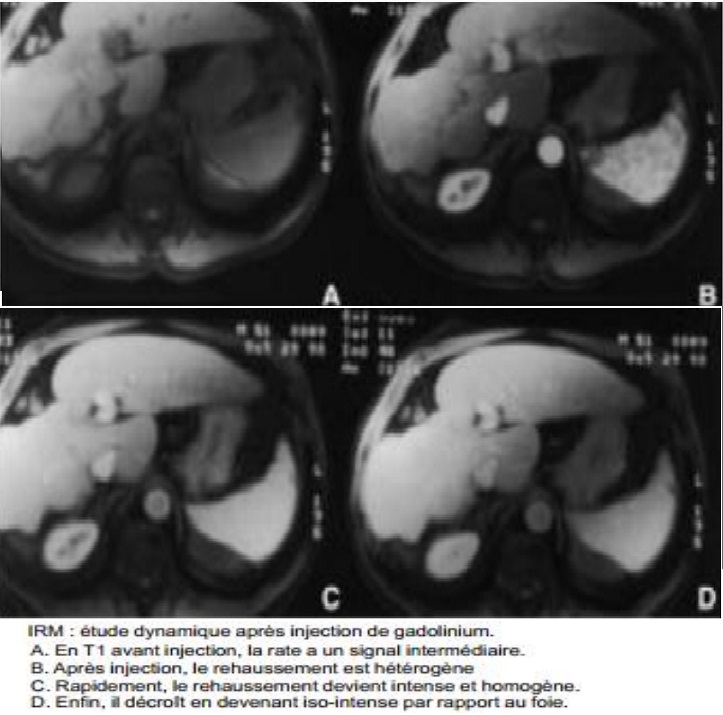

L’injection de

chelates de gadolium est necessite de explorer le temps

de rehaussement parenchymateuse tres precoce ( 15-25 sec

apres l’injection ) avec aspect de la rate heterogene et

puis rapidement devient homogene et isointense en

rapport avec le foie a la fin du temps de evacuation .

Aspect de la rate au temps de evacuation

apres injection de chelate de Gadolinium . Le

parenchyme de la rate est homogene et isosignal par

rapport au foie |

Dynamique de rehaussement de la rate apres

injection de Gadolinium intraveineuse |